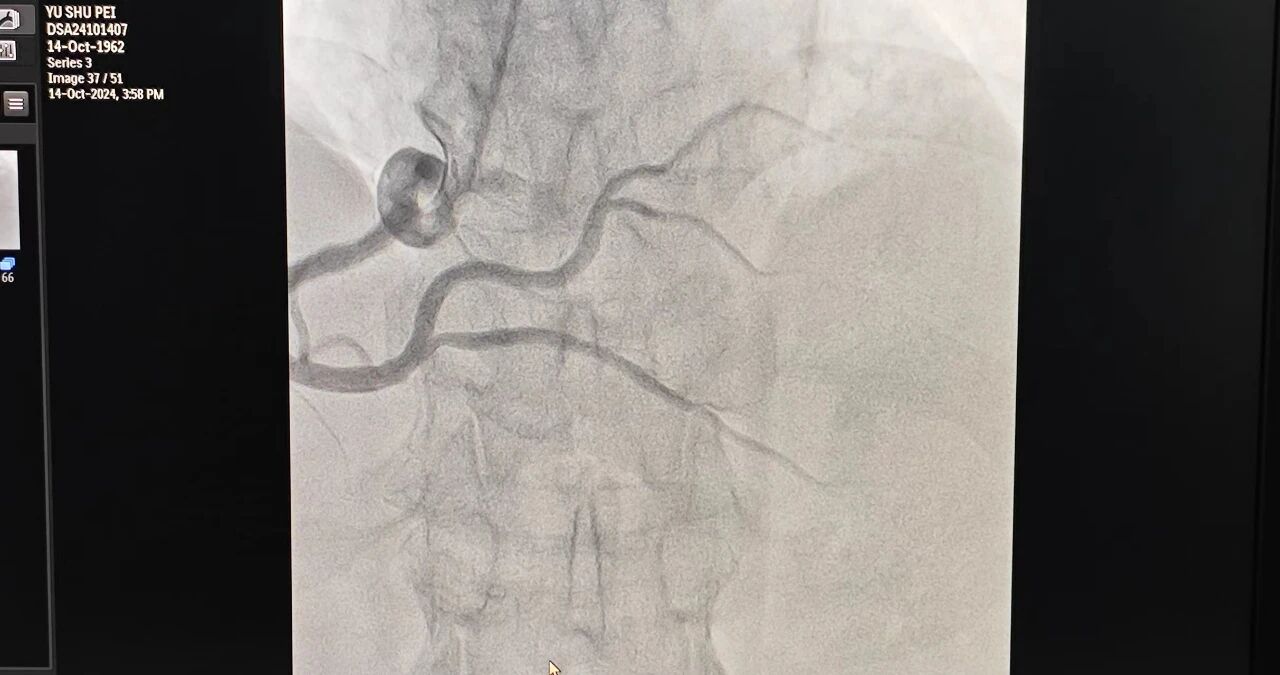

当天,医院特邀玉溪市人民医院心内科专家钱宝堂与玉溪市中山医院心内科主任梁梅共同合作,分别为4位饱受冠心病引发胸痛症状困扰的患者成功实施手术。目前,四位患者生命体征平稳,并已进入康复治疗阶段。

梁梅表示,这4台冠脉造影手术的成功开展具有里程碑意义,填补了玉溪市中山医院在冠心病介入诊疗领域的空白。随着新院区的正式投入使用,医院在手术人才、硬件设备、医疗环境等方面都得到了实质性的提升。目前,科室已能顺利开展择期冠脉造影及冠脉支架植入术、心脏临时起搏器、心律失常介入治疗(阵发性室上性心动过速、室性早搏、心房颤动等)等相关诊疗技术。